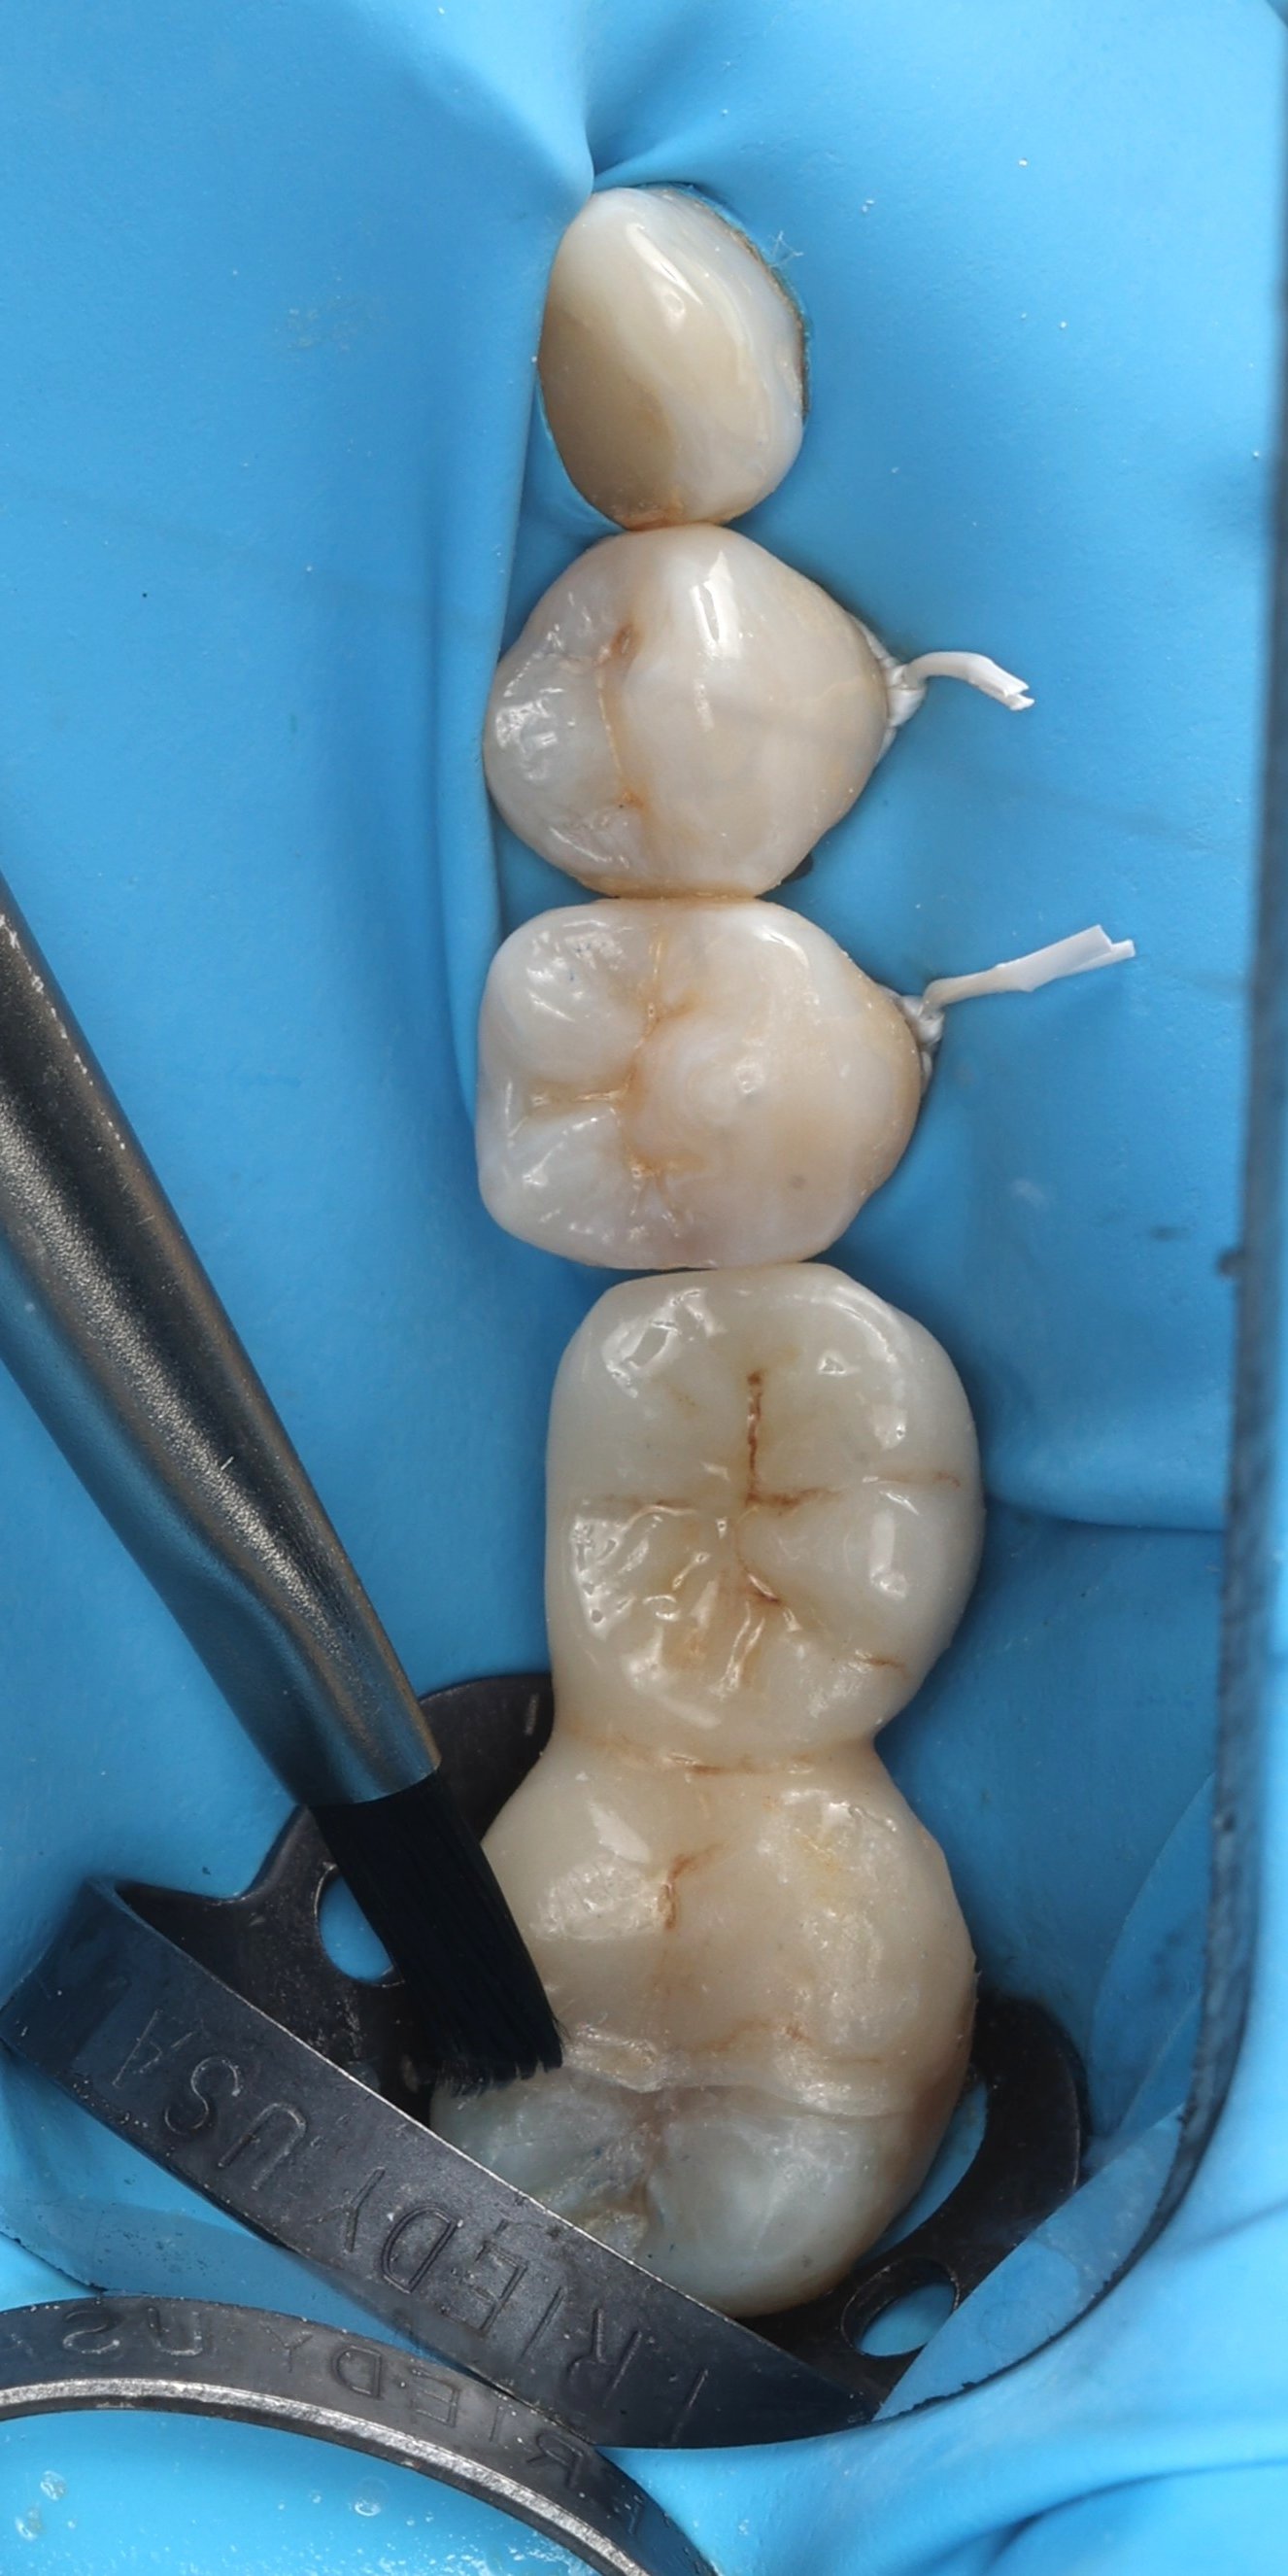

Relativement récents, les bridges collés cantilever postérieurs constituent une alternative fixe, fiable et véritablement minimalement invasive aux implants dans les secteurs postérieurs. Cette thérapeutique qui repose sur des indications bien précises est parfois débattue avec passion sur les réseaux sociaux ou dans les congrès scientifiques. Cependant des études cliniques existent, tout comme des recommandations validées dans des journaux internationaux. Leur succès repose sur des préparations et des principes biomécaniques rigoureux, pourtant simples à intégrer au quotidien. Cette intervention propose un guide clair et opérationnel incluant indications, étapes clés, protocoles d’adhésion et réglages occlusaux pour les mettre en œuvre avec confiance et reproductibilité.